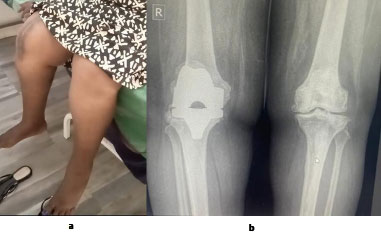

Standard anteroposterior and lateral radiographs were used to verify the proper positioning of femoral and tibial components (Fig. 5). However, a postoperative pangonogram, which would have allowed precise measurement of the mechanical axis (HKA), was not routinely performed due to its limited availability and high cost in our setting. This represents a limitation in the accurate evaluation of axial corrections in this study.

Postoperative anteroposterior and lateral radiographs showing proper positioning of the prosthesis in a patient operated on for primary knee osteoarthritis.

Postoperative radiograph showing a right total knee arthroplasty with the femoral component positioned perpendicular to the mechanical axis, corresponding to a mean α angle of 90° ± 4°.

A 67-year-old patient at postoperative day 28 following right total knee arthroplasty. The patient demonstrates knee flexion greater than 110 degrees, full extension, and satisfactory correction of the right lower limb axis.